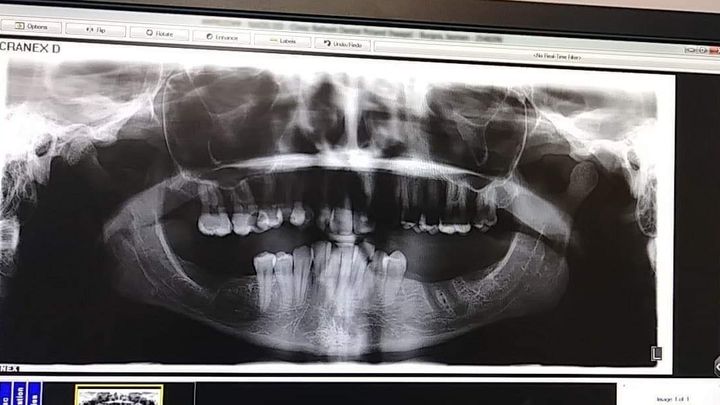

I need all my top teeth removed its covered. I need bonegrafting and healing dentures that is not. With 6 kids I cant pull funds from bills or their needs to do this. If I could have done it at a younger age I would have. Now I have time just not the money. if you can help thank you so much. Please no ride or negative comments. Ive been trying to get this done for many years. Ive been consumed by life completely and now I just need it done